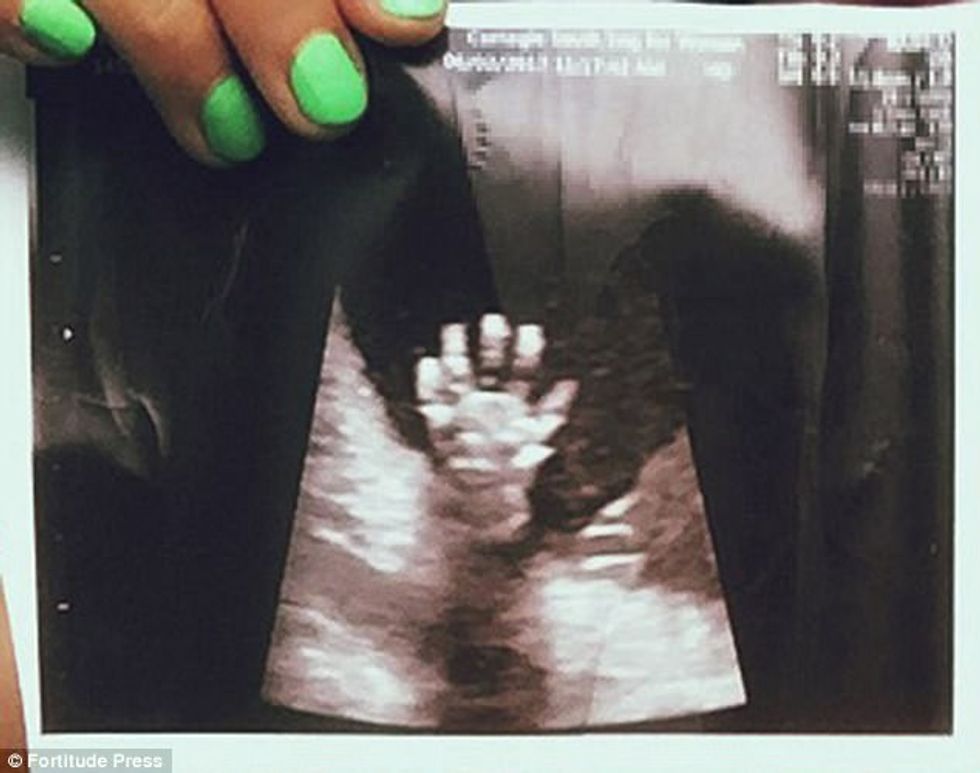

Pamje e pazakontë në pajisjen e ultrazërit: Fëmija i palindur, "përshëndet" me dorë (Foto)

Libby dhe Mathew Vlasic nga New Yorku, kanë mbetur të befasuar kur kanë parë fëmijën e tyre të palindur, që kishte ngritur dorën sikur donte t’i përshëndeste.

Por, derisa po bënin vizitat e zakonshme te mjeku, ata nuk mund t’i besonin syve kur panë imazhin që shfaqi ultrazëri.

“Sikur donte të thoshte se jam mirë dhe mos u brengosni për mua, vij së shpejti”, ka thënë Libby lidhur me rastin.

Madje, as ekspertët nuk kanë parë më herët që një fëmijë të kapet në këtë formë duke treguar qartë edhe gishtat e vegjël. /Telegrafi/